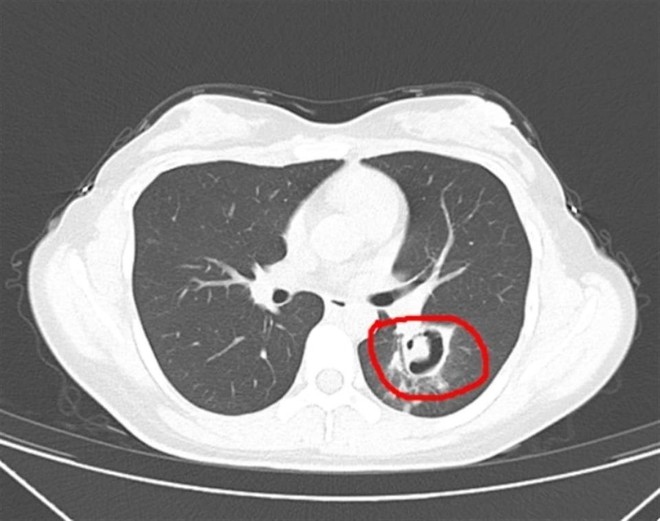

Sau một loạt kiểm tra, bác sĩ kết quả chụp CT phổi cho thấy những "chồi cây nhỏ" đã mọc ra từ phổi của cô Vương và họ nghi ngờ cô bị viêm phổi do nấm. Tiếp theo, bác sĩ tiến hành nội soi phế quản, phát hiện một lượng lớn mảng trắng trên thành đường thở. Sau khi xét nghiệm, xác định đó là Aspergillus.